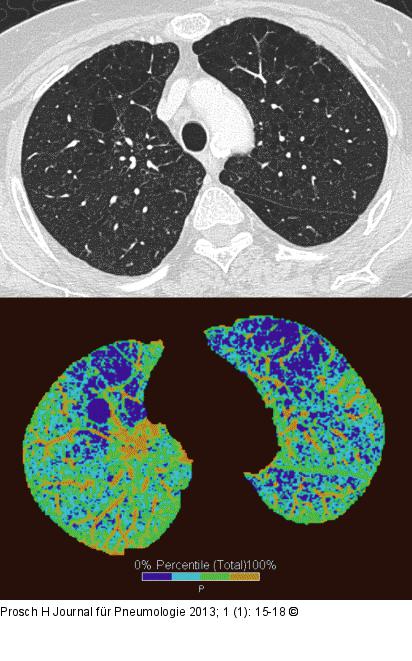

Abbildung 2: Computertomographie-COPD Quantifizierung eines Lungenemphysems. Lungenareale mit Dichtewerten unter -950 Hounsfield Units (HU) werden als Emphysem definiert und entsprechend farbkodiert dargestellt. |

Quantifizierung eines Lungenemphysems. Lungenareale mit Dichtewerten unter -950 Hounsfield Units (HU) werden als Emphysem definiert und entsprechend farbkodiert dargestellt. |